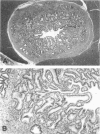

Enterocytozoon bieneusi is a common opportunistic pathogen of human patients with acquired immune deficiency syndrome (AIDS) causing significant morbidity and mortality. In a retrospective analysis utilizing conventional histochemical techniques, in situ hybridization, polymerase chain reaction, and ultrastructural examination, we identified 18 simian-immunodeficiency-virus-infected macaques (16 Macaca mulatta, 1 M. nemestrina, and 1 M. cyclopis) with Enterocytozoon infection of the hepatobiliary system and small intestine. The organisms were readily identified in the bile ducts and gall bladder by special stains and by in situ hybridization using a probe directed against the small subunit ribosomal RNA of human origin E. bieneusi. Infection of the biliary system was associated with a nonsuppurative and proliferative cholecystitis and choledochitis. Hepatic involvement was characterized by bridging portal fibrosis and nodular hepatocellular regeneration accompanied by marked bile ductular and septal duct hyperplasia. Ultrastructurally, all developmental stages of the organism were found in direct contact with the host cell cytoplasm; spores and sporoblasts contained a double layer of polar tubes. Sequencing of a 607-bp segment of the small subunit ribosomal RNA revealed 97 and 100% identity to two clones of small subunit ribosomal RNA derived from E. bieneusi of human origin. Extensive morphological and genetic similarities between the simian and human enterocytozoons suggest that experimentally infected macaques may serve as a useful model of microsporidial infection in AIDS.